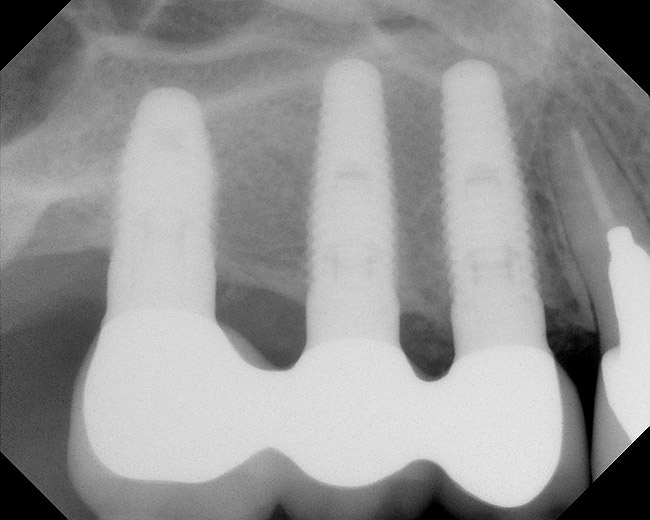

Figure 8  Radiographic confirmation of implant osteointegration into the new bone 14 months after the initial surgery.

Figure 8

Figure 9  Final implant-supported restoration.

Figure 9